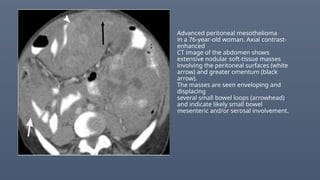

Advanced peritoneal mesothelioma

in a 76-year-old woman. Axial contrast-

enhanced

CT image of the abdomen shows

extensive nodular soft-tissue masses

involving the peritoneal surfaces (white

arrow) and greater omentum (black

arrow).

The masses are seen enveloping and

displacing

several small bowel loops (arrowhead)

and indicate likely small bowel

mesenteric and/or serosal involvement.